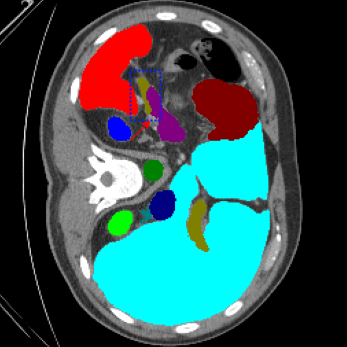

We begin by qualitatively inspecting our model. Figure 3 compares the output of LoGoNet to the best performing baseline model in BTCV dataset, i.e., DiNTS Search (more qualitative comparisons can be found in appendix section 11). We see that our model particularly excels in segmenting organ boundaries. This can be attributed to our effective strategy for extracting local-range dependencies, which plays a crucial role in extracting details from input data. Our model’s adeptness in capturing long-range dependencies allows it to grasp contextual information that extends over significant distances within the data. Simultaneously, its proficiency in handling short-range dependencies ensures precision in capturing localized patterns.